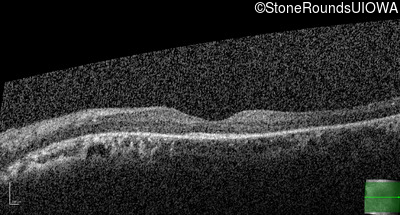

Optical Coherence Tomography - Left - 20/40 -1

Exemplar / OCT Stack

OCT Stack